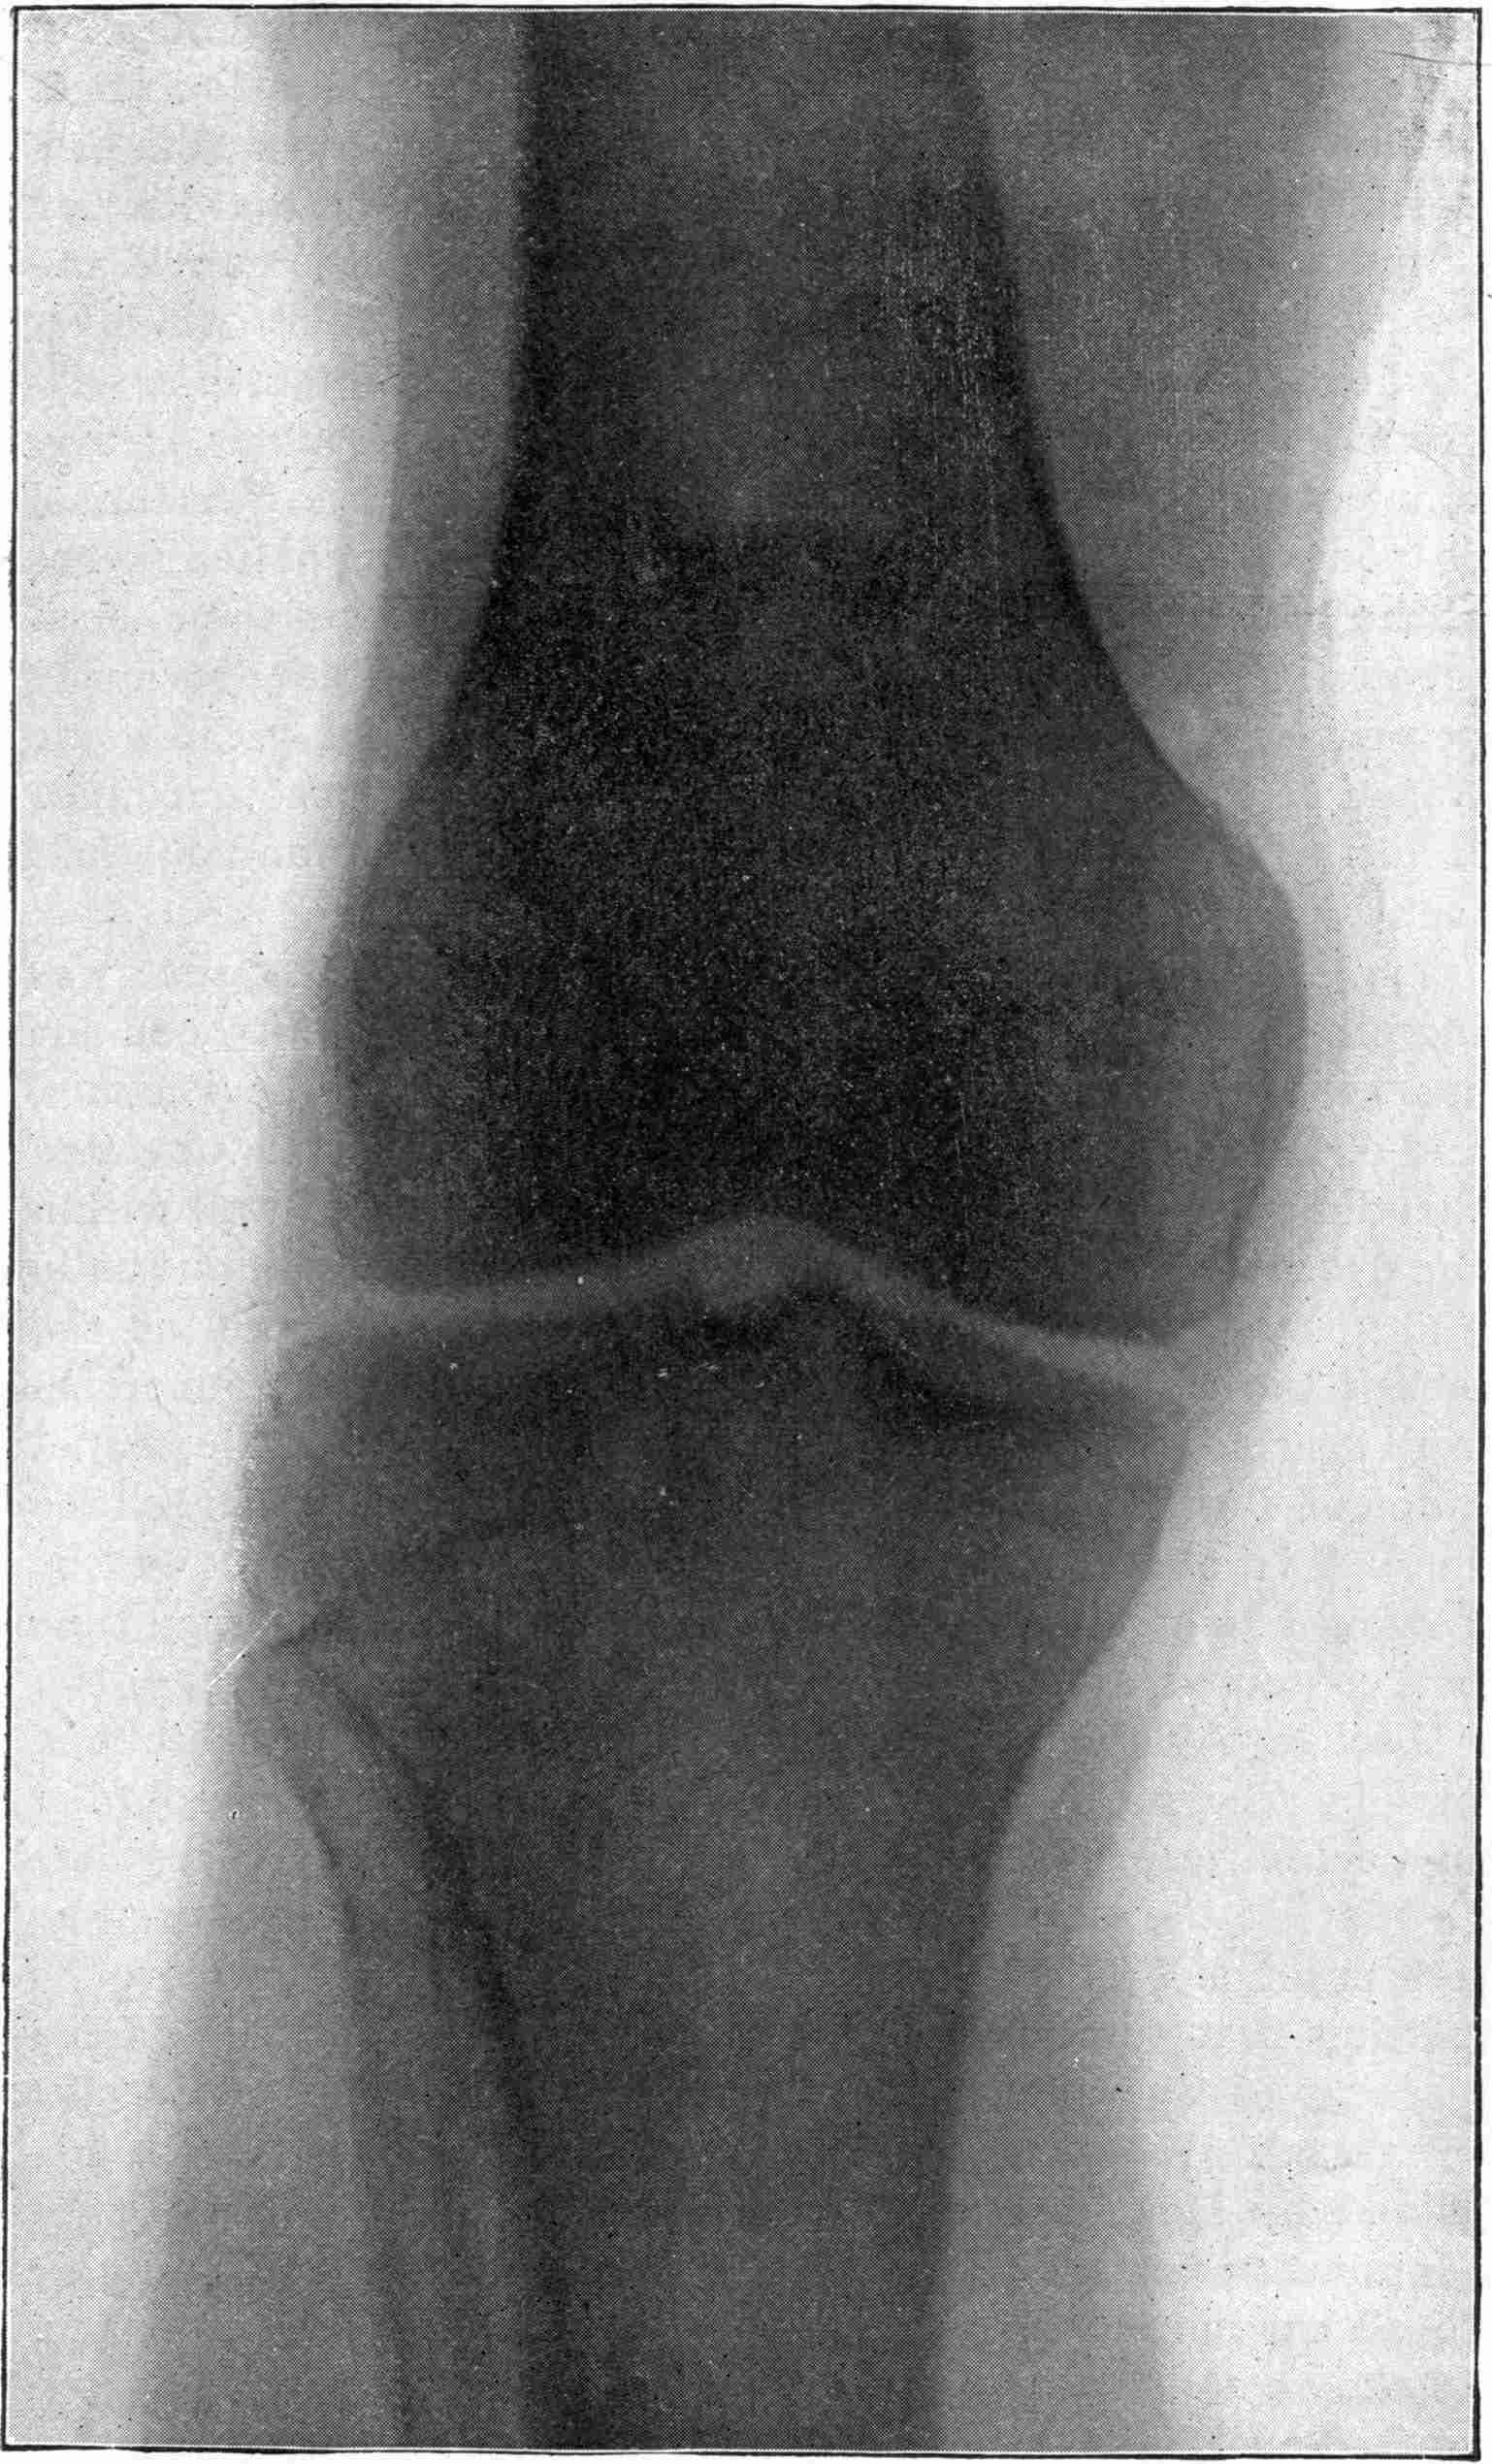

Fig. 4.—Knee, Knickerbocker Buttons, Bullet in Femur.

FROM SCIAGRAPHS BY PROF. DAYTON C. MILLER. § 204.